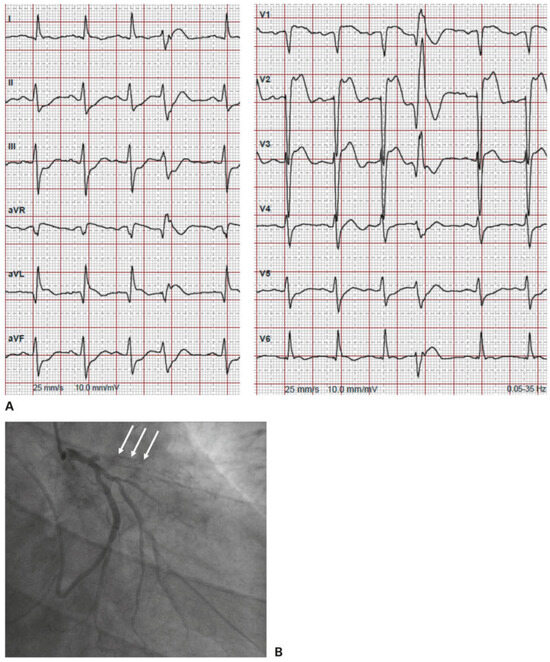

Figure 5.

A. 12-lead ECG from patient 2 after cardioversion showing anterior ST-segment elevation myocardial infarction. B. Coronary angiography showing in-stent thrombosis of the left anterior descending artery (white arrows).

Regardless of the correct identification of ventricular tachycardia, from the emergency point of view, the question of whom you treat first depends on the patient’s stability. Patient 2 was unstable on arrival at the ED. He was immediately transferred to the shock room where the advanced cardiac life support (ACLS) algorithm for stable/unstable tachycardia was applied (Figure 4, adapted from [4]). As the patient had hypotension, altered mental state and ischaemic chest discomfort, he immediately underwent synchronised cardioversion, in accordance with the algorithm. Most important is to record a 12-lead ECG after successful cardioversion, which in our case showed an anterior ST-segment elevation myocardial infarction (Figure 5A). The patient was directly transferred to the heart catheterisation laboratory, where an in-stent thrombosis of the left anterior descending artery was found and treated with percutaneous transluminal coronary angioplasty and stenting. He remained stable after this intervention (Figure 5B).